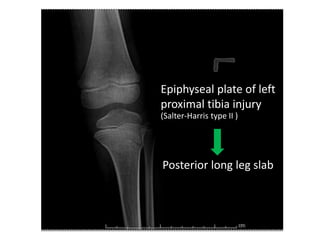

Epiphyseal plate of left

proximal tibia injury

(Salter-Harris type II )

Posterior long leg slab

Epiphyseal plate ofleft proximal tibia injury (Salter-Harris type II )

Epiphyseal plate ofleft proximal tibia injury (Salter-Harris type II ) Posterior long leg slab